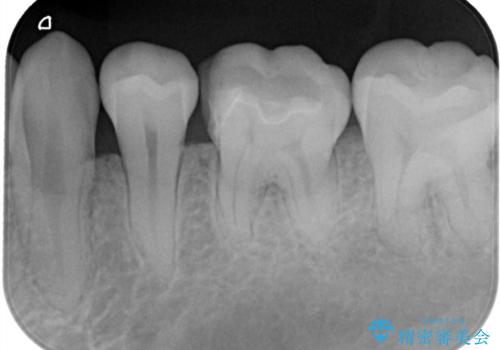

- 「銀歯を白くしたい」を主訴に来院された患者さんです。 左下6番に銀歯を被せてあり、一部分が欠けている状態でした。

銀歯と虫歯を除去しハイブリッドインレーで治療を行いました。